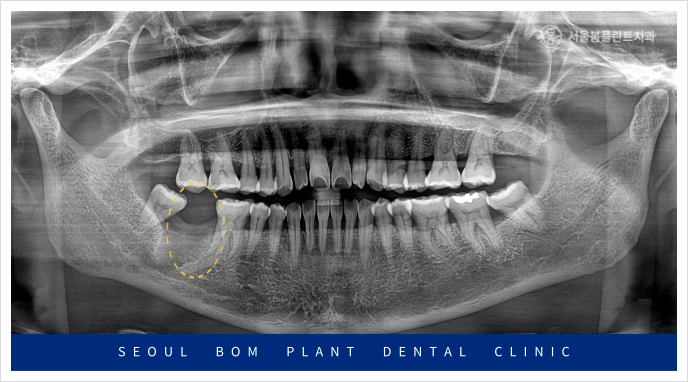

이 환자분의 상태를 정밀하게 검사하기 위해

파노라마 촬영을 진행한 결과,

아래턱 오른쪽 두 번째 어금니(#47) 주변에

심각한 염증이 확인되었습니다.

이 염증이 하치조 신경관까지 영향을 미쳐,

방치할 경우 주변 조직과 다른 치아에까지

영향을 미칠 수 있는 위험한 상황이었습니다.